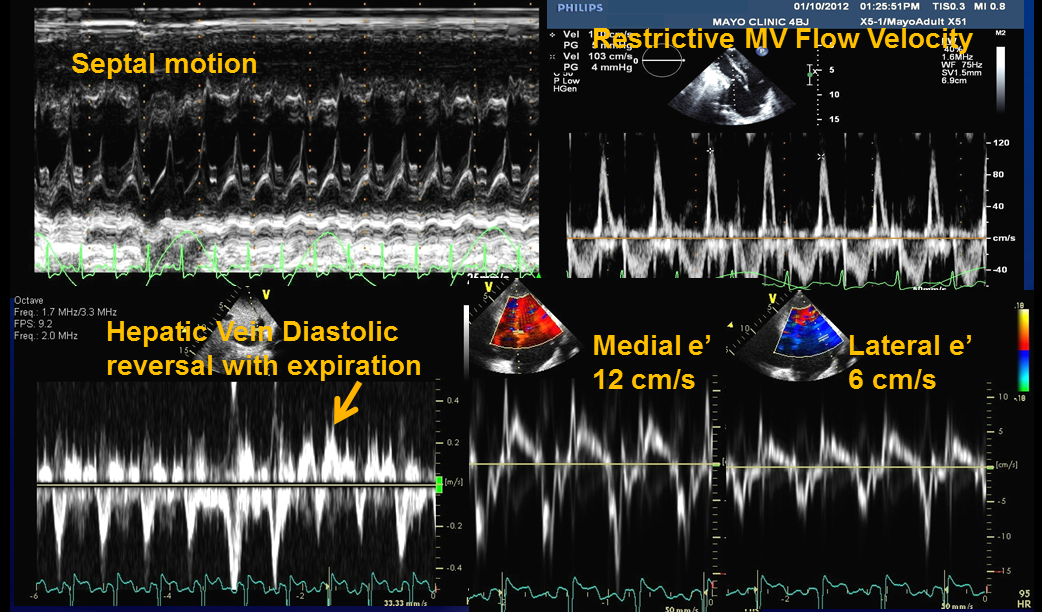

1. Ventricular septal motion abnormality (from ventricular interdependence)

2. Medial mitral annulus e' velocity ≥ 9 cm/sec

3. Hepatic vein expiratory diastolic reversal ratio ≥ 0.79 (Figure)

4. Restrictive mitral inflow velocity (E/A ratio > 0.8)

5. Plethoric inferior vena cava

1 + either 2 or 3 =  87% sensitive and 91% specific